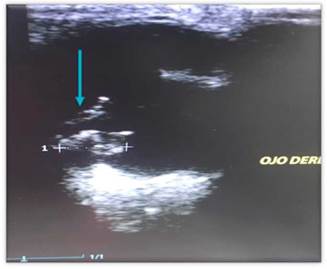

En la ecografía ocular se evidencia masa en cuerpo ciliar derecho de 0,92 por 0,52 cm, no se observa infiltración de masa en cámara vítrea, o anormalidad en retina, ni desplazamiento de cristalino. Se lleva a cabo extracción de humor acuoso, y se envía muestra para citología a laboratorio Corpavet (Figura 5 y 6). Los resultados citológicos confirman depósitos de gránulos de pequeño tamaño, uniformes, negruzcos, compatibles con pigmento melánico y agrupados. Los hallazgos citológicos son morfológicamente compatibles con melanoma (Figura 7). Posteriormente se realiza patología confirmando por laboratorio Corpavet, el diagnóstico fue melanoma uveal (Figura 8), la citología ocular se realizó antes de la enucleación.

En las (Figuras 12, 13 y 14) se aprecia cómo a través de la ecografía se logra evidenciar un tumor intraocular que daña la estructura anatómica, mediante una imagen heterogénea en el cuerpo ciliar.

De acuerdo a lo anterior, en el ojo derecho del paciente, se observa gracias a la ecografía, una masa con una densidad heterogénea, bien definida en el cuerpo ciliar derecho (Figura 14), insinuante de una neoplasia a nivel uveal, como diagnóstico.